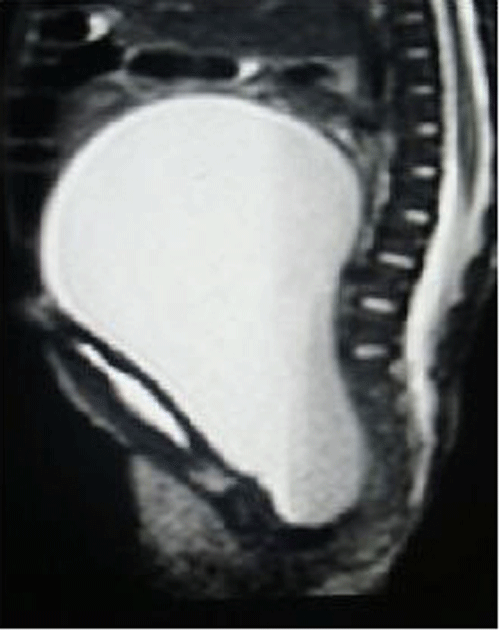

USG suggested a large hydrometrocolpos. MRI scan (Fig. 4), showed large hydrometrocolpos with atretic lower vagina and associated bilateral hydronephrosis. Genitogram revealed no communication between bladder and vagina. Echocardiography suggested a VSD with a PDA. A cutaneous vaginostomy was done and post-operative recovery was uneventful. At 4 month follow up, child is thriving well and is awaiting definitive vaginal reconstruction.

Figure 4: MRI of hydrometrocolpos with vaginal atresia.